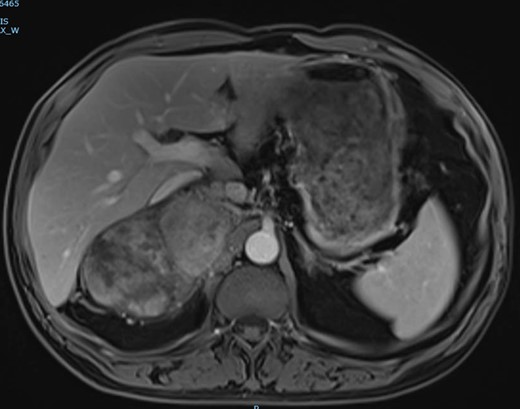

The magnetic resonance imaging (MRI) found the mass, which was measured at 85 × 60 × 160 mm, heterogeneous, with isointense and T1-weighted hyposignal (Fig. 2), isointense and T2-weighted hypersignal (Figs 3 and 4), and diffusion-weighted heterogeneous hypersignal. After injection of the contrast product, the mass did not appear to be hypervascular, and uptake was more pronounced in the late phase, indicative of a fibrous nature. The FDG-PET scan showed a hypermetabolic mass with SUVmax of 6.3. Finally, after excess secretion of catecholamines had been ruled out, a CT-guided biopsy was performed, with the histological analysis concluding that a schwannoma was highly probable.